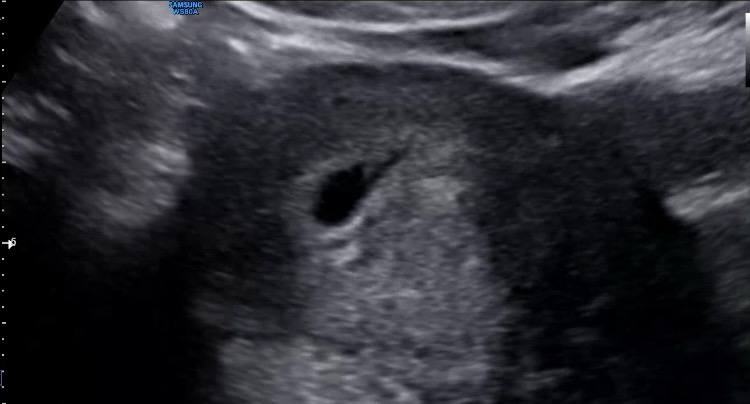

6주차 초반에 심장소리 듣고 왔어요 :) 저기 아주 껌딱지만한게 110 bpm 이라는게 뭔가 벌써 자랑스러운ㅎㅎ 2주뒤에 병원 오라고 하는데 그때까지 잘 자라면 좋겠어요! 언능 젤리곰 사진으로 보고 싶네요

저도 오늘 6주4일차 120bpm 심소듣고왔어요!!ㅎ 저도 2주뒤에 설 잘보내고 보자고 하시던데.. 2주가 2년같을듯해요…ㅋ